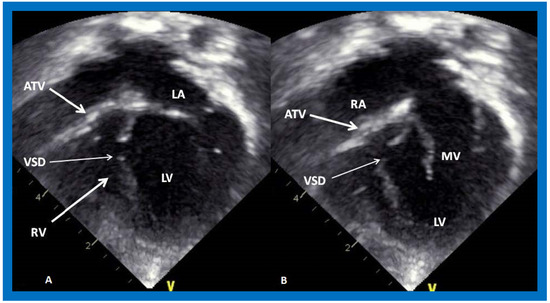

Figure 6. Selected video frames from apical four chamber, two dimensional echocardiographic views of a patient with tricuspid atresia showing an enlarged left ventricle (LV), a small right ventricle (RV) and a dense band of echoes at the site where the tricuspid valve echo should be (ATV) (thick arrow) with a closed (A) and open (B) mitral valve. A moderate sized ventricular septal defect (VSD) (thin arrow) is shown. LA, left atrium; RA, right atrium. Reproduced from Reference [29].

Applsci 11 09472 g006

On 2D echocardiography, the atretic tricuspid valve is visualized directly as a dense band of echoes at the site where the tricuspid valve should be, as shown in Figure 4, Figure 5 and Figure 6; this echo appearance is that of the most frequent muscular type of TA. This anatomy is better demonstrated in apical and subcostal four chamber views than in other views. The other anatomic types (Figure 1), namely, membranous, valvular, Ebstein’s, atrioventricular septal defect, and unguarded tricuspid valve with muscular shelf, are rare and may also be recognized on 2D echocardiography. An example of an atrioventricular septal defect type of TA [30] is demonstrated in Figure 7; in this example, a 2D echocardiogram demonstrated an ostium primum ASD with a common atrioventricular valve and a small RV (Figure 7a,b); the entry into the RV appeared to be occluded by a leaflet of the common atrioventricular valve. Left ventricular and right atrial cineangiograms confirmed these findings [30]. Evaluation of the crux cordis (Figure 8) on a 2D echocardiogram (subcostal four chamber view) may help to distinguish the various anatomic types (Figure 1) from each other. In the muscular type of tricuspid atresia, a dense band of echoes is seen where the normal tricuspid valve should be (Figure 8A). In membranous types of tricuspid atresia, a thin membrane is seen instead (Figure 8B). In both these types, the anterior leaflet of the detectable atrioventricular valve is attached to the left side of the interatrial septum (Figure 8A,B). In the atrioventricular septal defect type of tricuspid atresia, the crux cordis is abnormal and cannot be identified; the anterior leaflet of the detectable atrioventricular defect is attached to the anterior wall of the heart, and a large atrioventricular valve leaflet occludes the entry of the RA into the RV (Figure 8C). Based on these observations, it was concluded that 2D echocardiographic (and angiographic) features help to differentiate the atrioventricular canal type of tricuspid atresia from the classic muscular tricuspid atresia cases [30].

Following the demonstration of the atretic tricuspid valve, the sizes of the cardiac chambers are evaluated both by M-mode (Z scores) and 2D echocardiography; an enlarged RA, LA and LV and a small RV are seen (Figure 4, Figure 5 and Figure 6). Pulsed (not shown) and color Doppler (Figure 9) studies are helpful in illustrating right to left shunt across a PFO or an ASD.